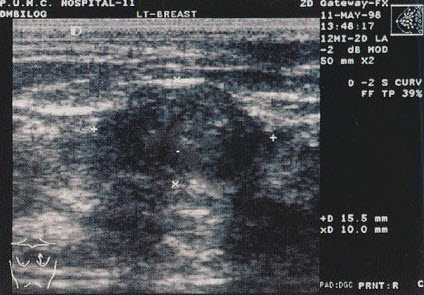

男,6岁,阵发性腹痛,呕吐数小时就诊。PE:肠鸣音亢进,呈气过水音。根据超声声像图诊断为()

发现一侧乳房无痛性肿块3天,腋窝及颈部可触及数个黄豆大包块,乳腺超声声像图如上,最可能的诊断是()

A.乳头状导管癌

B.髓样癌

C.乳腺淋巴瘤

D.乳腺囊性增生

E.以上都不是